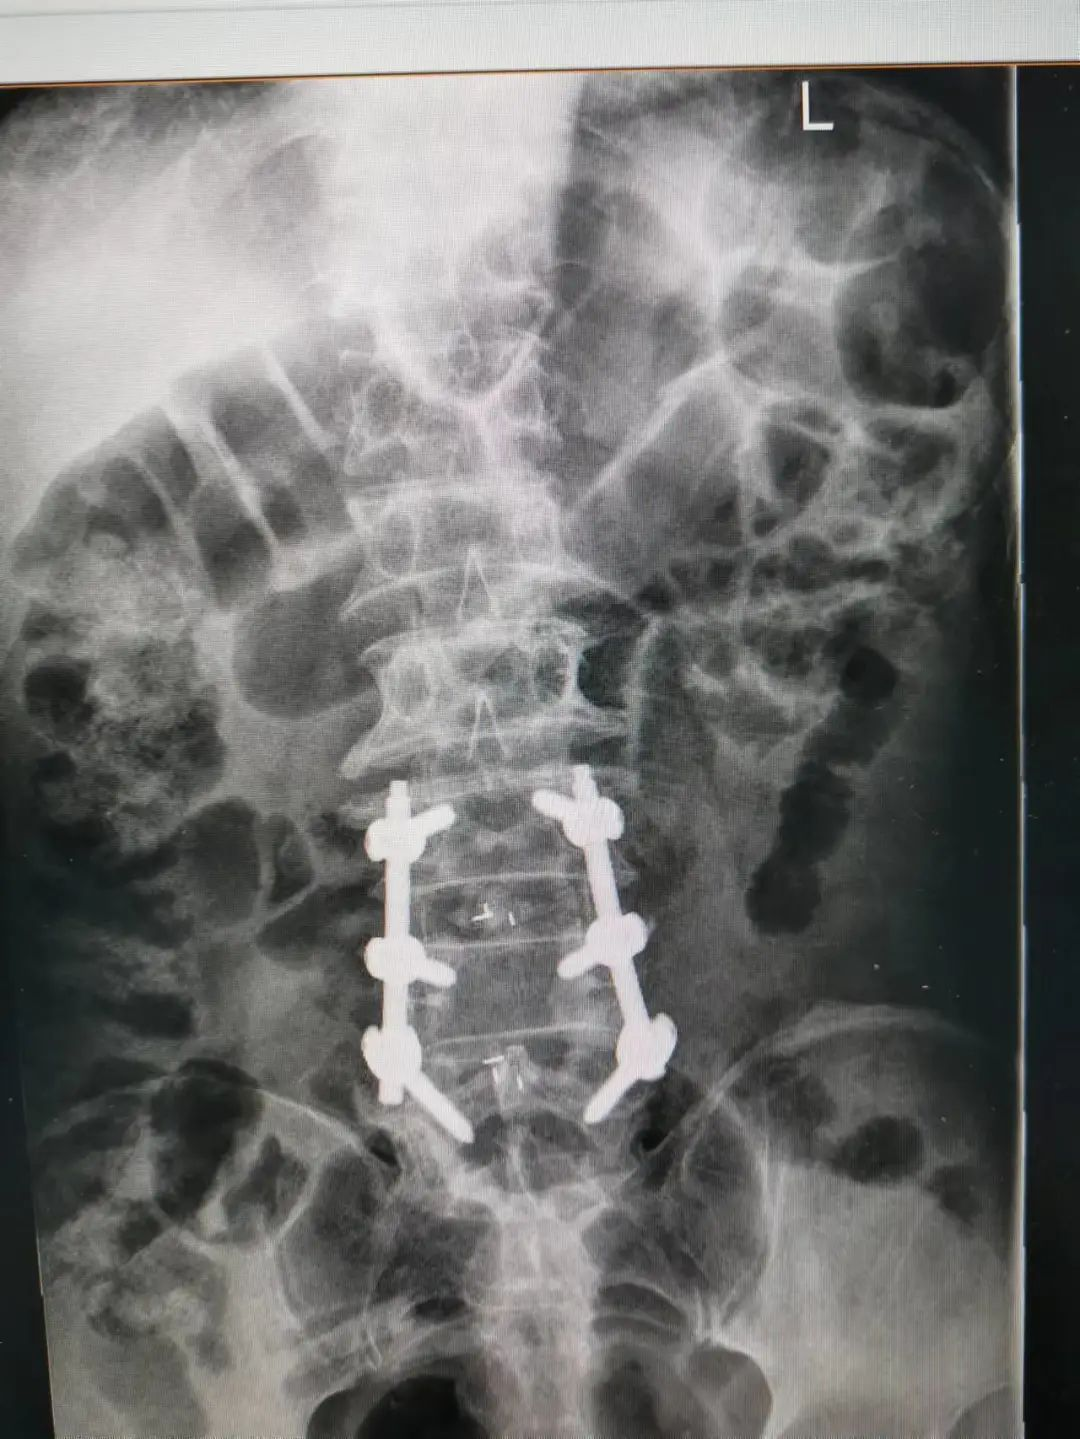

楊先生腰椎管狹窄癥拍片

由于楊先生的病情嚴重,需住院治療。楊先生入院后,瀘州市中醫(yī)醫(yī)院骨傷二科科主任楊陳一制定了手術(shù)計劃,決定脊髓型頸椎病的手術(shù)從前路切開減壓,頸3/4 、頸4/5、 頸5/6、 頸6/7椎間盤切除,椎間融合,鋼板內(nèi)固定術(shù)手術(shù),而腰椎管狹窄癥經(jīng)后路切開減壓,腰3/4、腰4/5椎同盤動除,椎間融合、釘棒系統(tǒng)內(nèi)固定術(shù)。